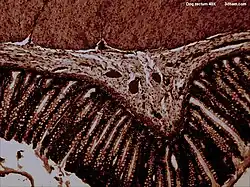

Microanatomy

The microanatomy of the wall of the rectum is similar to the rest of the gastrointestinal tract;[9] namely, that it possesses a mucosa with a lining of a single layer of column-shaped cells with mucus-secreting goblet cells interspersed, resting on a lamina propria, with a layer of smooth muscle called muscularis mucosa. This sits on an underlying submucosa of connective tissue, surrounded by a muscularis propria of two bands of muscle, an inner circular band and an outer longitudinal one.[10] There are a higher concentration of goblet cells in the rectal mucosa than other parts of the gastrointestinal tract.[9]

The lining of the rectum changes sharply at the line where the rectum meets the anus. Here, the lining changes from the column-shaped cells of the rectum to multiple layers of flat cells.[9]